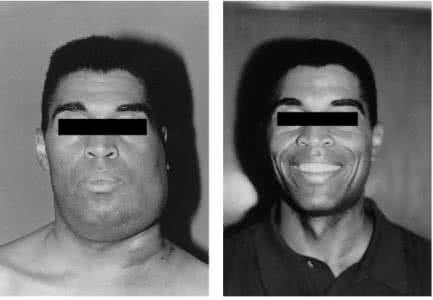

慢性淋巴結炎圖片

慢性淋巴結炎 (38)

慢性淋巴結炎 (39)

慢性淋巴結炎 (4)

慢性淋巴結炎 (40)

慢性淋巴結炎 (41)

慢性淋巴結炎 (42)

慢性淋巴結炎 (43)

慢性淋巴結炎 (44)